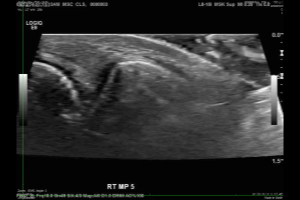

Using a small transducer, a sonographer recorded video images of 400 MPJs, as participants attempted to crack their knuckles. The sonographer also captured static images of each MPJ before and after participants tried their hands at cracking.

Two radiologists interpreted the ultrasound images, looking for sonographic evidence that would correlate with the audible cracks, which occurred in 62 of the 400 joints imaged.

"What we saw was a bright flash on ultrasound, like a firework exploding in the joint," Dr. Boutin said. "It was quite an unexpected finding."

Using the flashes on the ultrasound images, the radiologists were able to identify the joints with audible cracks with at least 94 percent specificity.

"There have been several theories over the years and a fair amount of controversy about what's happening in the joint when it cracks," Dr. Boutin said. "We're confident that the cracking sound and bright flash on ultrasound are related to the dynamic changes in pressure associated with a gas bubble in the joint." As for which comes first — the cracking sound or the flash of light — Dr. Boutin said that more research is needed.